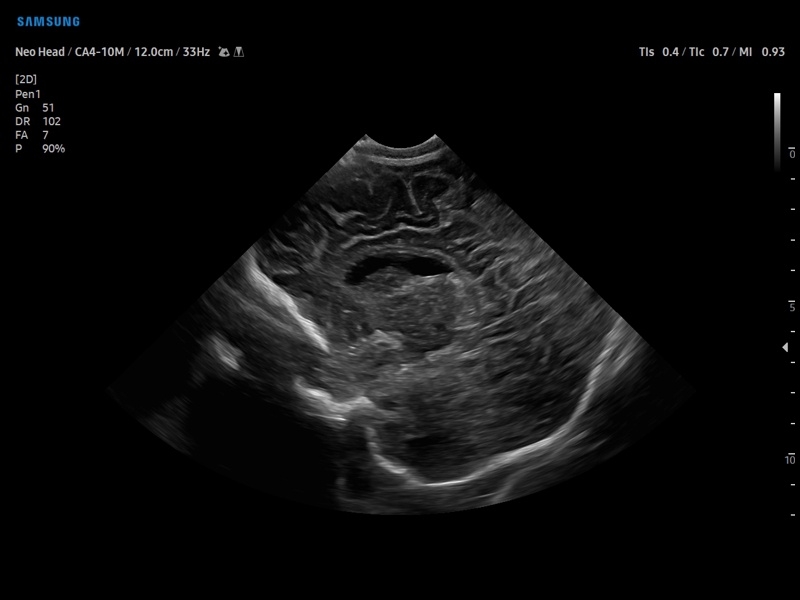

• Модуль5D CNS– программа автоматического построения основных срезов головного мозга плода в режиме объемного сканирования.

• Педиатрия и неонатология

• Транскраниальные исследования